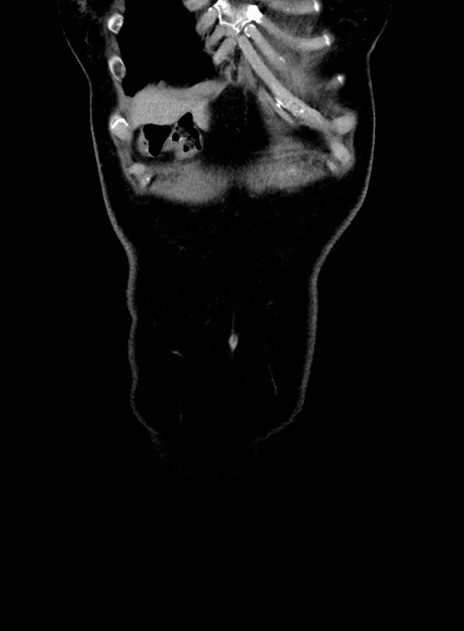

症例9(冠状断像)

【症例】 60歳代女性

【主訴】むかつき、みぞおちの痛み

【現病歴】3日前よりむかつきがあり、食事がとれない。

【既往歴】糖尿病

【身体所見】発熱なし、心窩部圧痛軽度あるも、腹膜刺激症状なし。

【データ】WBC 7400、CRP 1.92